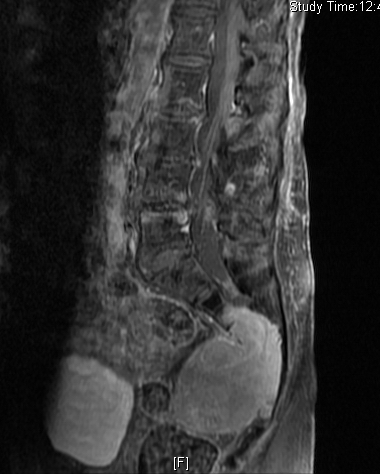

MRI (Fig. 4-10)

• Isointense or hypointense on T1W (Fig. 4-5)

• Hyperintense on T2W (Fig. 8 & 9)

• Hyper enhancement with gadolinium (Fig. 6 & 7).

Fig. 4-10: MR image of a chordoma shows a destructive bone lesion in the sacrum that is hypointense on T1W images, hyperintense signal on T2W and enhancement of the lesion after gadolinium.